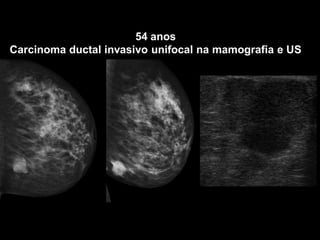

54 anos

Carcinoma ductal invasivo unifocal na mamografia e US

Estadiamento localInformações clínicas relevantesDetecção de focos tumorais ocultos na mamografia e na USModificação na terapia cirúrgicaRedução na taxa de recidiva e aumento na sobrevida?